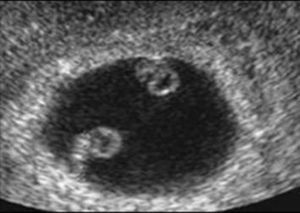

Determination of amnioticity is difficult until 8 weeks of gestation. Before that time the amnion is still too close to the embryo and is identifiable in only 50% of the cases.9 The amnions appear as thin echogenic membranes surrounding the two embryos inside the celomatic cavity (Fig. 3).

Lack of visualization of the amniotic membranes after 8 weeks allows the diagnosis of monochorionic monoamniotic twins. In this case the number of yolk sac seen may be one or two depending on the timing of cell division.10